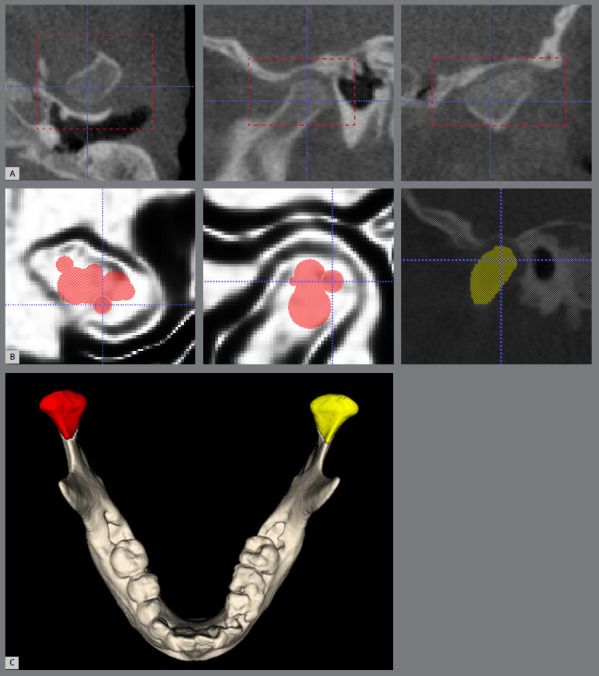

Methods: Cone-beam computed tomography (CBCT) of 47 UCLP patients were included, and divided into two groups (prepubertal stage and pubertal stage). The mandibular ramus height (Co-Go), mandibular body length (Go-Me), total mandibular length (Co-Me), gonial angle (CoGoMe), the volume of the mandibular condyles, and lateral chin deviation were evaluated. The cleft side (CS) and noncleft side (NCS) were compared using the paired t-test for dependent samples. Chin deviation and its possible association with specific sides were evaluated using the Mann-Whitney and Fisher's Exact tests, respectively. The significance level was set at 5%.